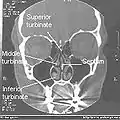

Nasal concha/turbinate

Lateral wall of nasal cavity, showing ethmoid bone in position. (Superior and middle in pink, and inferior in blue.)